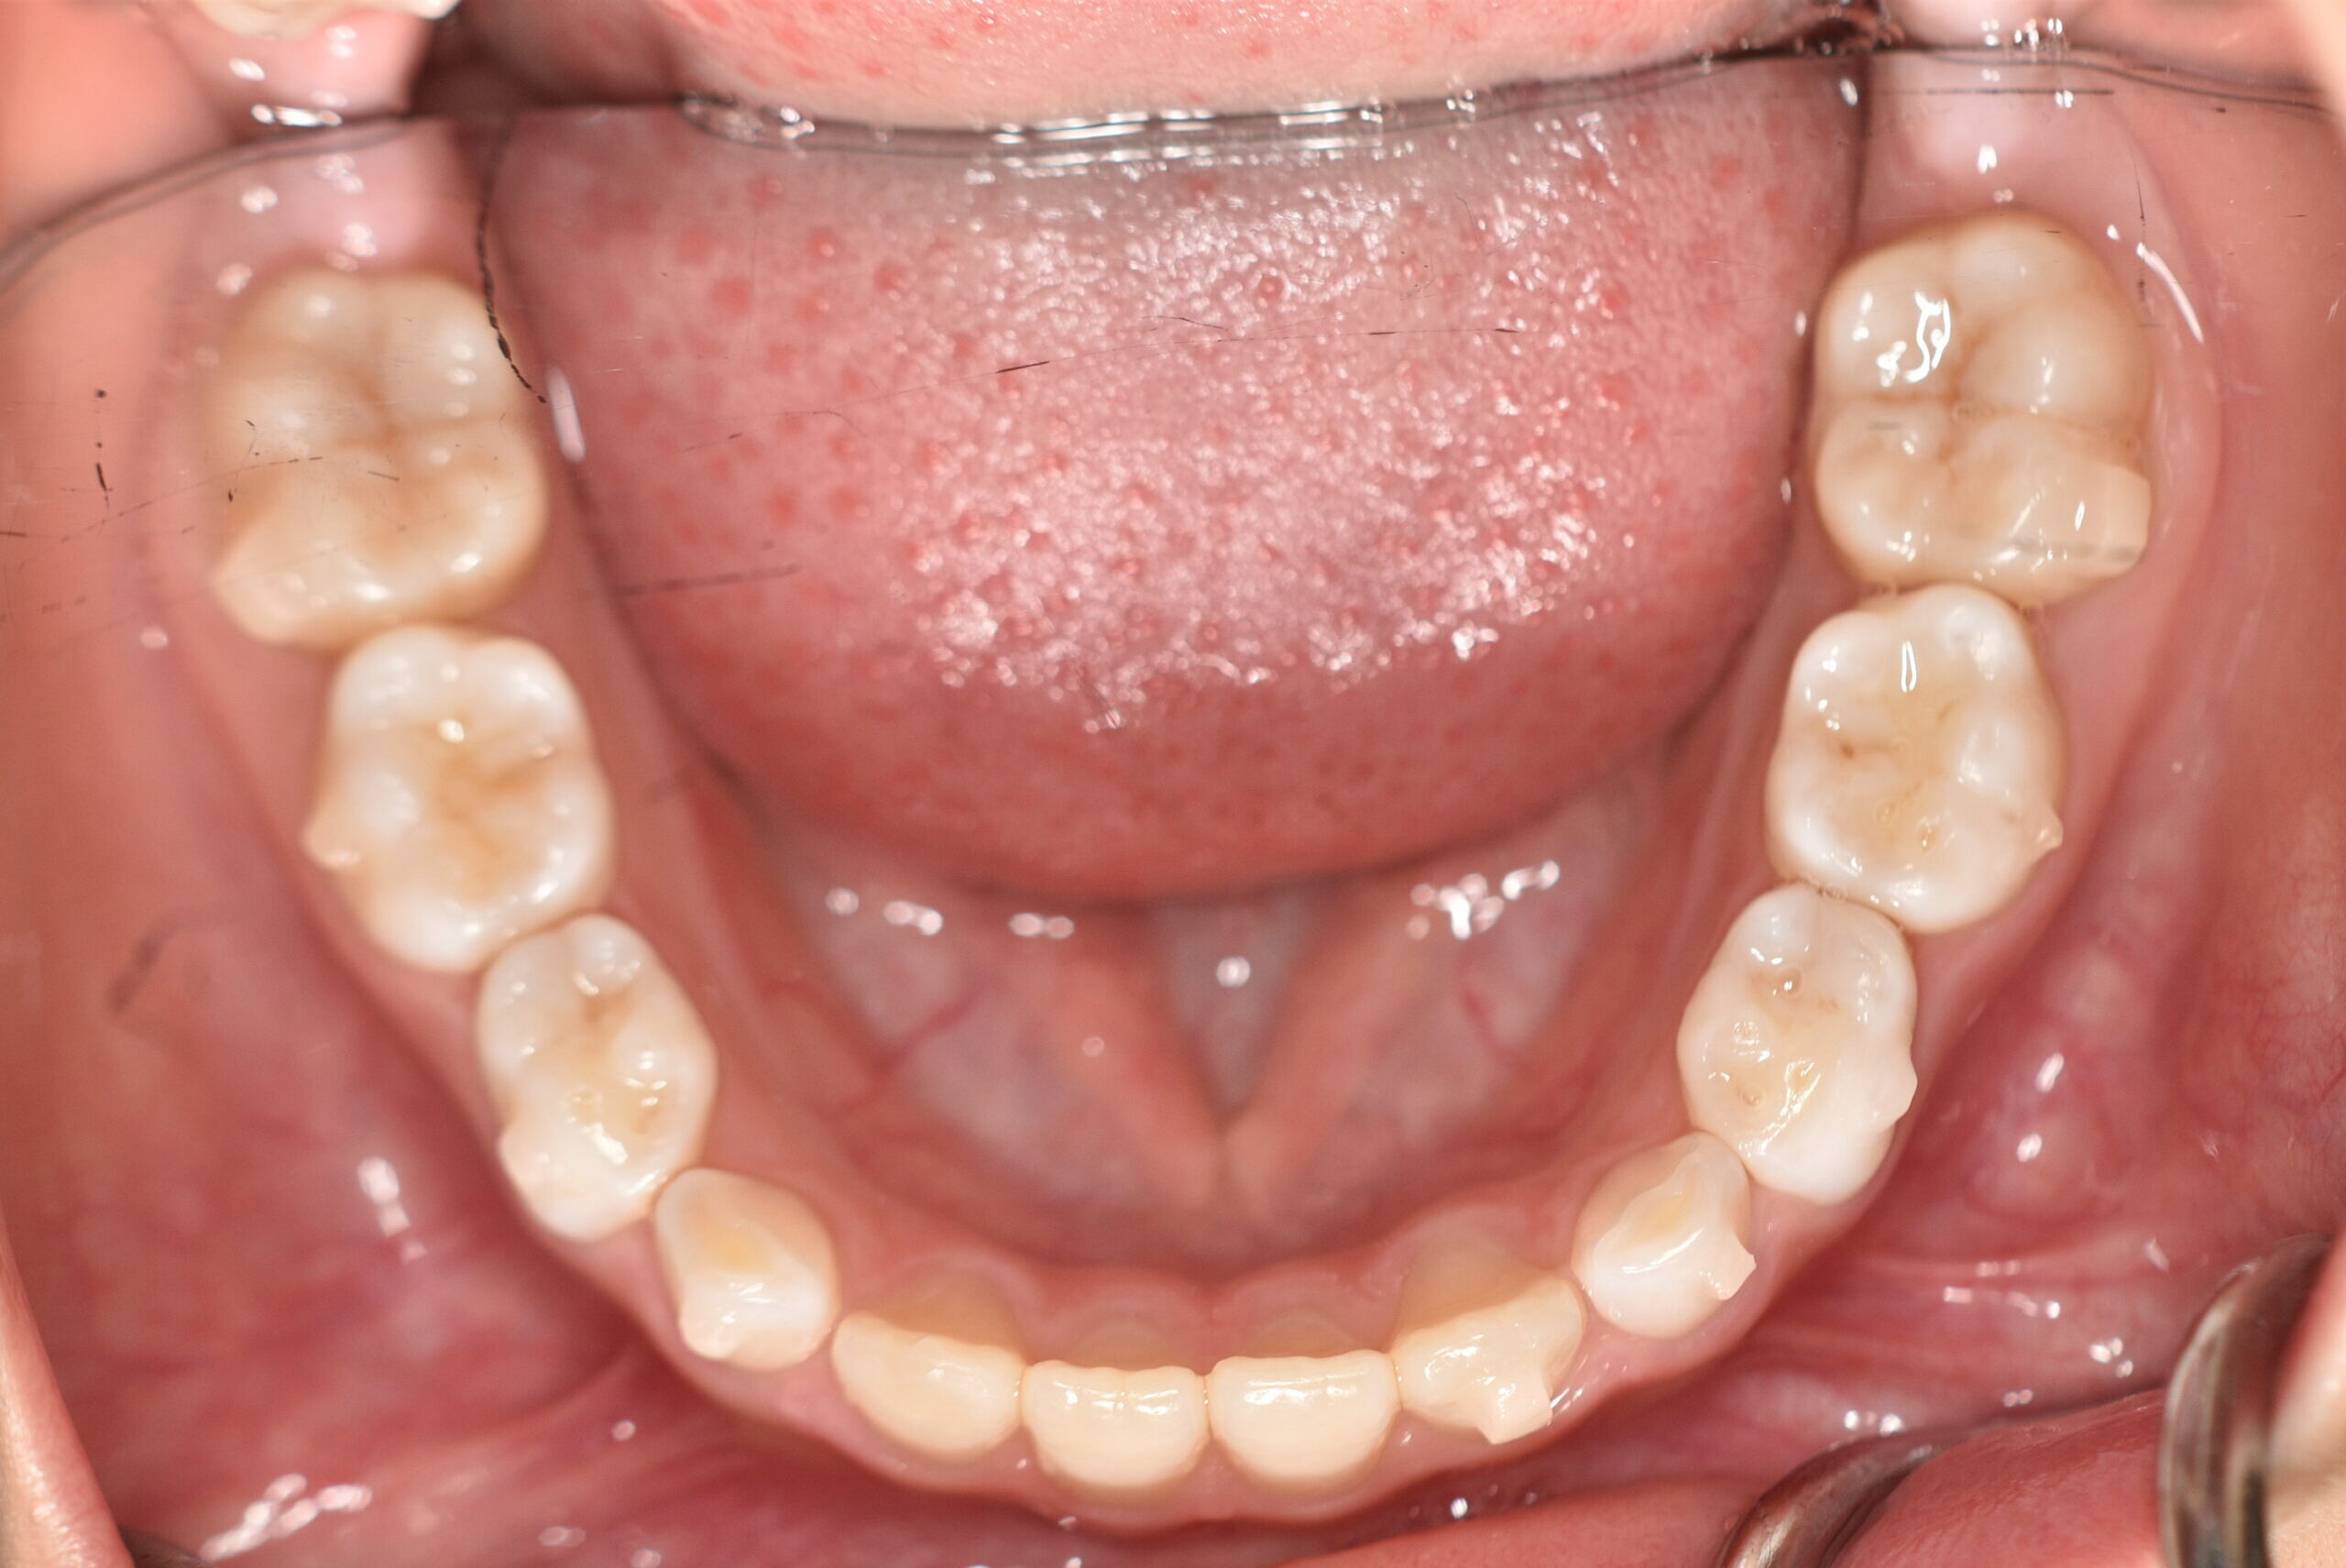

初診時

症例 症例 症例 症例

動的治療終了時

年齢

9歳 性 別 女性

治療期間 7ヶ月 費 用 矯正施術料:750,000円

調整料:4,000円/月

治療内容の詳細 初診時9歳の女児で、歯のがたつきを気にされ来院されました。

検査の結果、前歯部叢生を伴うアングルⅠ級不正咬合と診断しました。

治療としてはマウスピース矯正(インビザラインファースト)で配列を行い、上下顎の側方拡大と萌出スペースを確保しました。

治療期間は、7ヶ月でした。

今後、側方歯生え変わりまで経過観察を行います。